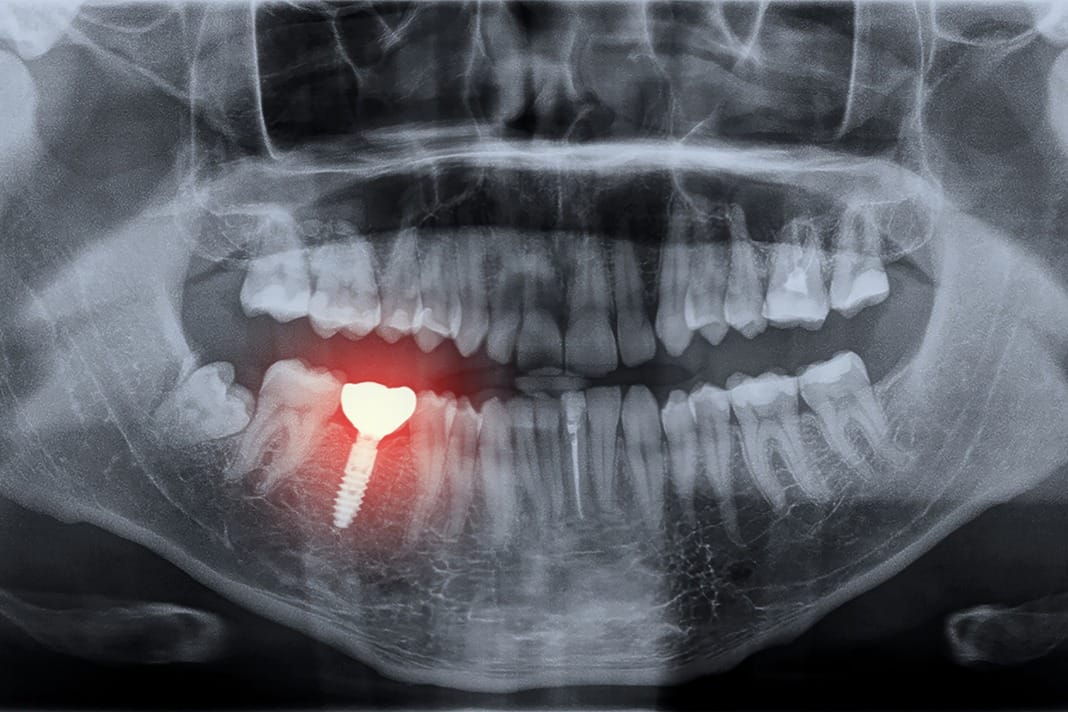

Some researchers believe “that the difference in support at both ends of the system places the implant at risk for complications.”5 This is a case example of a three-unit implant-supported bridge in place of teeth # 4-5 with obvious limitations for adequate hygiene attributable to design. When looking at the clinical image, the restoration may look appropriate, but the radiographs suggest otherwise.

Something else that needs consideration when examining dental implant restorations for hygiene accessibility is retention. This is a three-unit cement-retained implant tooth-supported bridge. Not only does the design of this bridge make hygiene challenging, but if you examine the radiograph closely, you will notice residual cement, which presents another risk factor for plaque accumulation and peri-implant disease.

Note radiographic residual cement and peri-implantitis with pus exudation.